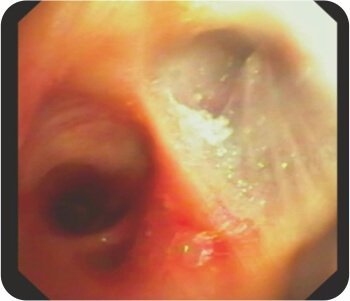

সক্রিয় হেমোপটিসিস

ডান উপরের ব্রঙ্কাসে স্ফিগট বসানো

ডান উপরের লোব ব্রঙ্কাসে স্ফিগট বসানো